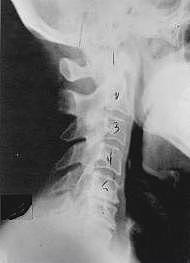

This is a side x-ray view of the neck. As with all the pictures you will see on this page, the patient is looking to the right of the screen, so you are viewing the right side of their neck. We will call this picture a "near normal" spine. Compare this spine with the ones you will see below on this page. Notice the normal forward curve of the neck. This curve helps absorb shock. Notice how each of the disc spaces between C2 (second bone in neck) and C7 are thick and even, this again is normal. Also notice how the front portions (right on the x-ray) of each of the vertebrae (called the 'body' of the vertebrae) are fairly square with clear and well defined borders. This type of arrangement is normal in the neck. Normal vertebrae in other parts of the spine also have similar characteristics to what we see here. When subluxations occur and are left uncorrected, ongoing relentless changes occur that result in damage to the structure and function of the spine along with nerve damage and the resulting problems caused from improper nerve supply.